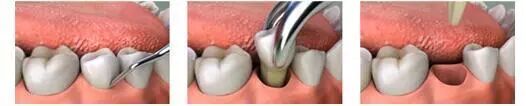

二、别老用舌头舔伤口

当吐了纱球后,牙槽窝已经止血了。这时候血凝块已经形成。如果在经过唾液或者喝水的冲刷,血凝块又会分解,最终导致血凝块脱落和再出血。

因此,拔牙24小时内不要漱口和刷牙,喝水也不能用力,更不能经常用舌头舔伤口。